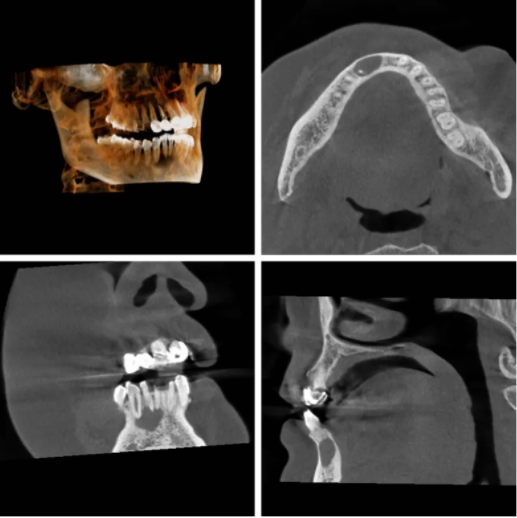

近日,患者易女士因反复牙齿咬物不适来娄星区人民医院(娄星区妇幼保健院)口腔科就诊,科室主任龙晓明通过询问病史,对易女士仔细进行了口腔检查,发现右下尖牙牙冠变色,伴有裂纹,叩诊不适,通过口腔CBCT检查后发现:右下前牙区颌骨内可见约1.5x1.0x0.7cm大小的椭圆形均匀透射阴影,初步诊断为根尖周囊肿。龙主任与易女士沟通后确定了治疗方案:患牙常规根管治疗后行根尖囊肿摘除,根尖周刮治及根管倒充填手术,术后易女士感觉非常好。

龙晓明主任表示:口腔检查建议常规拍摄口腔全景片或CBCT片,可以发现一些隐匿性的口腔问题,尤其是颌骨囊肿,埋伏阻生牙等。口腔CBCT可以从三维角度判断囊肿的大小和范围,有时根尖囊肿发展比较大时,并不仅仅侵犯一个牙的根尖,有可能侵犯旁边牙根或其它重要的解剖结构,这对治疗计划的制定和治疗效果的判断都是有一定帮助的;根尖周囊肿如果范围比较大,除了患牙做根管治疗之外,还需要通过根尖手术,把囊肿剥离或把炎性病变彻底刮除清理掉,这样才有可能会被治愈。

口腔CBCT是目前国际最先进的口腔科专用CT,在业界被誉为神奇的"慧眼",具有扫描快、范围大、精度高、应用广、放射剂量极低的特点。可以通过其强大的处理软件功能以及面部匹配技术迅速形成清晰逼真的三维图像,在智齿拔除、牙种植测量、多生牙定位、颞下颌关节疾病、颌骨三维重建、根管治疗评估、正畸设计等方面提供精准的诊断与治疗依据。

口腔CT可以从三维角度对组织情况进行反映,可以发现口腔X光片的投照角度不能发现的、或者更细微的病变;它的三维重建效果能够对骨组织情况、下颌关节情况进行准确评价,协助医生进行手术前方案设计,以及术后科学评价。

CBCT克服了一些传统影像学的局限,如影像重叠,扭曲等,通过三维重建能够准确的显示患牙自身病变及其与周围组织的关系。

CBCT通过对患者360度旋转扫描,获得三维图像,对患牙可进行多角度多层面观察,避免影像重叠而造成漏 诊。CBCT对牙根折裂的诊断明显优于X线根尖片。